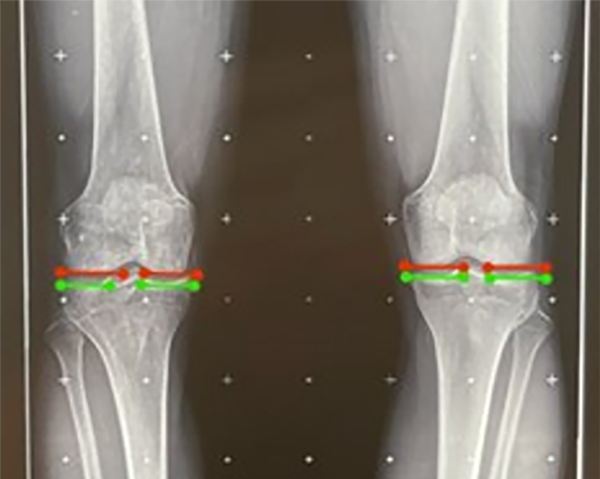

El test de mal alineamiento continúa con dos anexos: el 1 se realiza para descartar la subluxación de la articulación de la rodilla y el anexo 2 evalúa la alineación condilar.

Figura 7: Se observa en líneas roja y verde la línea articular de cada cóndilo femoral y cada platillo tibial, se evidencia que son colineales, por lo cual no hay una incongruencia articular.